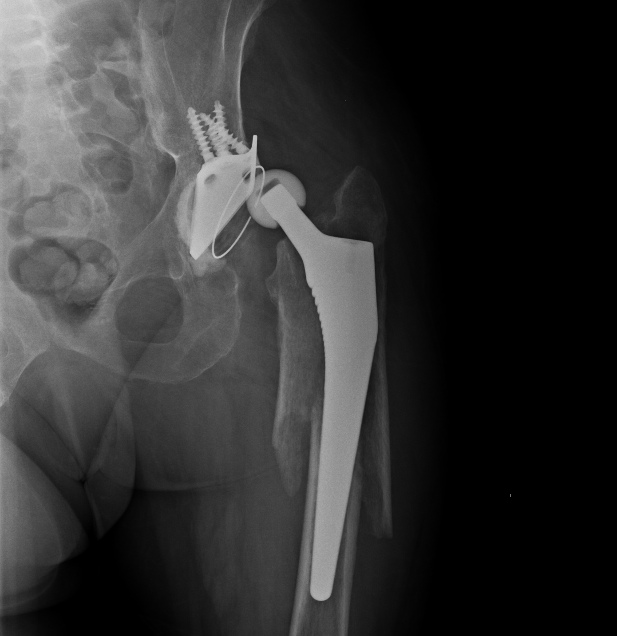

Надежность, если все правильно сделано, как минимум достаточная для любых нагрузок. Не понял насчет "был бы тех же размеров" - это и есть оскольчатый перелом, вот снимок до операции. Никаких верхних доступов, все закрыто. Принципы АО - вещь переменная, в конце 2013 г. издана аошная книжка про перипротезные переломы, там уже есть про эту методику. Цемент иногда действительно приходится удалять, но мы уже в 3 случаях смогли сделать без обнажения конца ножки, вытаскивали кусочки цемента через доступ для гвоздя. Не "ревизия ad oculus" подтверждает верность тактики, а результат. Представлен хороший непосредственный результат, будем надеяться, в дальнейшем он сохранится. А тактика верная - не обязательно одна. Могут быть и три првильных.

в этом случае перелом перипротезный на уровне эндопротеза с нестабильностю ножки. Это требует замены ножки. ПЛАСТИНА в любом случае требует большей инвазии. Здесь я за ножку вагнера.

Вот и было сделано нечто типа длинной ножки. Только закрыто и с запиранием.

Не являюсь спецом по перипротезным переломам, но у нас как правило или остеосинтез или ревизионная ножка - что послужило здесь поводом сочетать оба метода?

"Операция выполнялась в соответствии со всеми принципами АО" - судя по количеству серкляжей вы с этой фразой немного погорячились. Кстати тоже: пластина позволяет вводить винты спереди и сзади от ножки протеза - почему предпочли не винты, а проволоку?